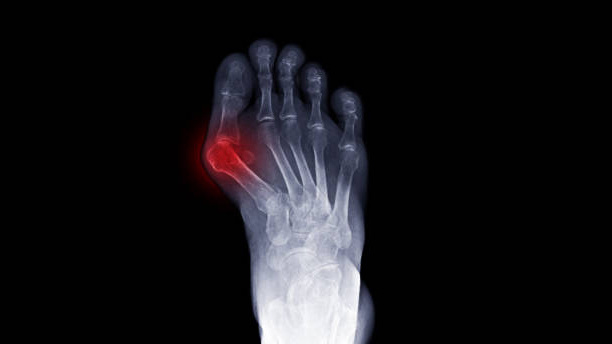

Hallux valgus je deformita, při které se palec nohy vychyluje směrem k ostatním prstům. Současně se v oblasti palcového kloubu vytváří vystouplá a často bolestivá kostní prominence, která bývá citlivá na tlak a tření.

Hallux valgus je deformita přednoží, při které se palec vychyluje směrem k ostatním prstům a v oblasti palcového kloubu vzniká bolestivé vystouplé místo. Potíže se často projevují bolestí, tlakem v obuvi, otlaky a omezením chůze.